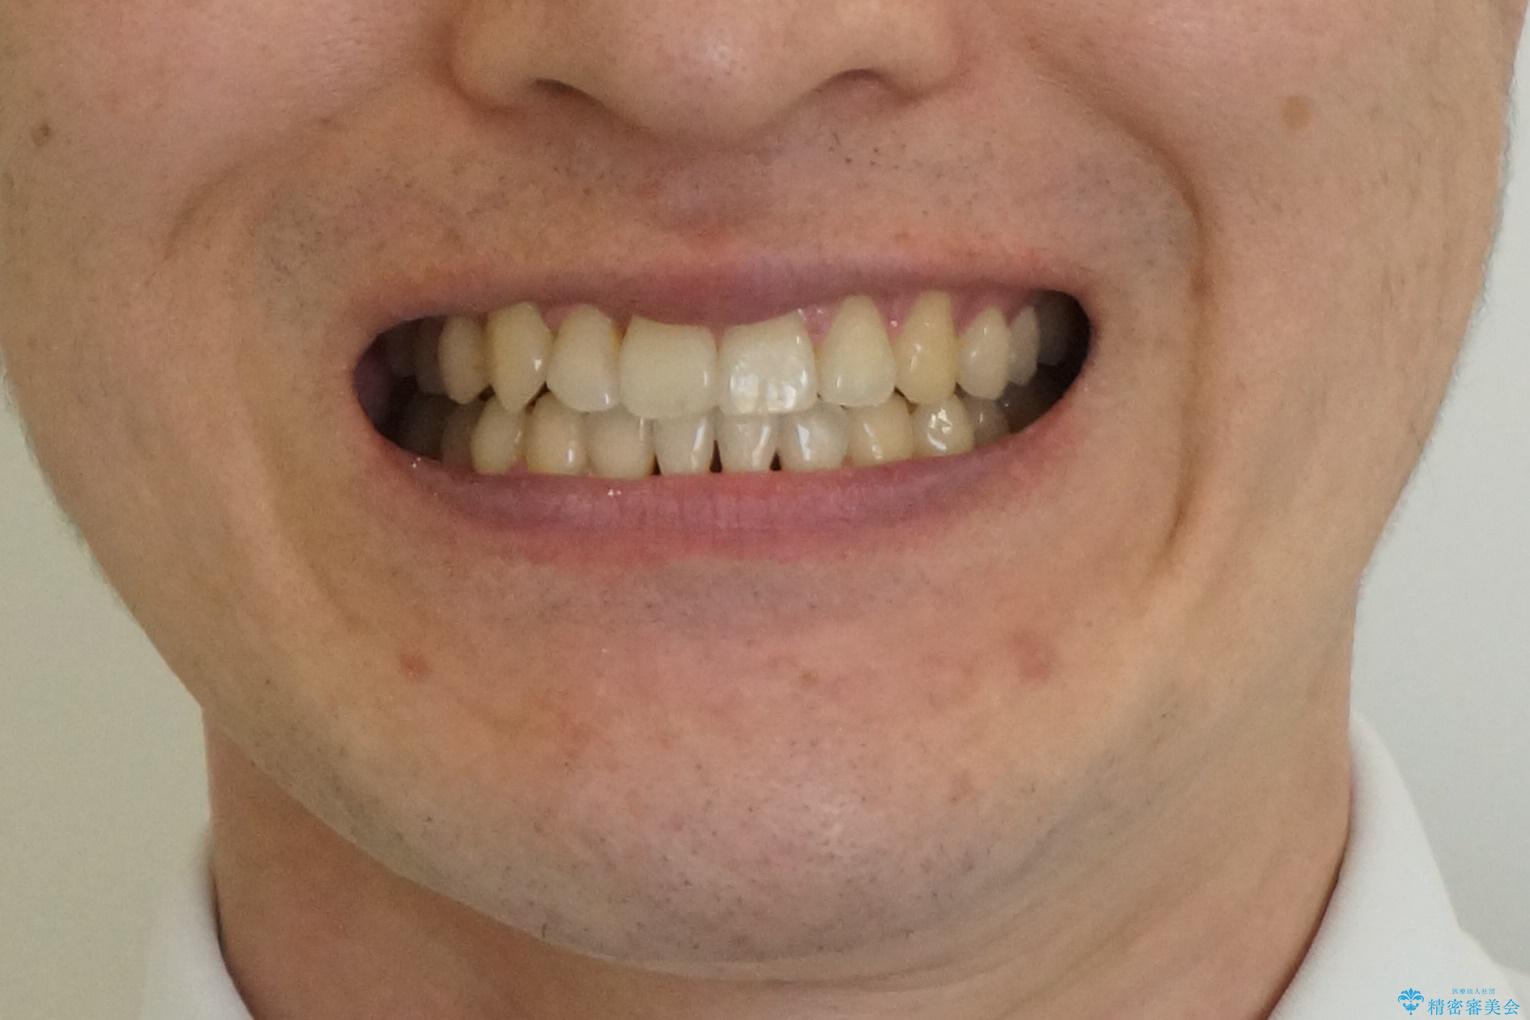

- 右上の前歯が内側に入っているのを気にして来院。

右上の奥歯を後ろに移動して、前に出すスペースを確保してから並べました。

奥歯を後ろに送るために、矯正用インプラントを使用しています。

前歯が内側に入っていると、笑った時にそこが黒くなり、歯が抜けたように見えます。

口を開けたとき、笑顔の印象が大きく変わり、大変喜んでいただけました。